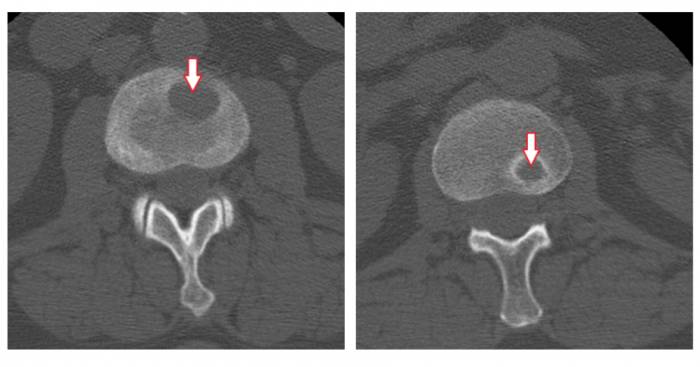

Грыжи межпозвонковых дисков при КТ позвоночникаклассифицируются в зависимости от их локализации. Так, выделяют задние, латеральные и передние грыжи дисков — в зависимости от того, в какую сторону выпадает межпозвонковый диск. Задние грыжи в свою очередь могут быть центральными (диск выбухает кзади по средней линии), медиаолатеральными (диск выбухает в латеральный карман справа либо слева), фораминальными (диск выбухает в межпозвонковый канал). Грыжа диска может быть также внутрикостной (по типу т. н. грыжи Шморля) — при этом происходит пролабированиепульпозного ядра в тело позвонка с проламыванием его замыкательной пластинки.Грыжа Шморля при компьютерной томографии позвоночника выглядит как дефект тела позвонка, отграниченный плотным склерозированным «ободком». Редко встречается также вариант интрадурального пролапса (грыжи), когда секвестр распространяется под твердую оболочку спинного мозга.

Пример парамедианной грыжи межпозвонкового диска в пояснично-крестцовом сегменте позвоночника при компьютерной томографии (грыжа диска отмечена стрелкой). В диске визуализируются также включения газа («вакуум-фемонен»), отмечены красной звездочкой «*».